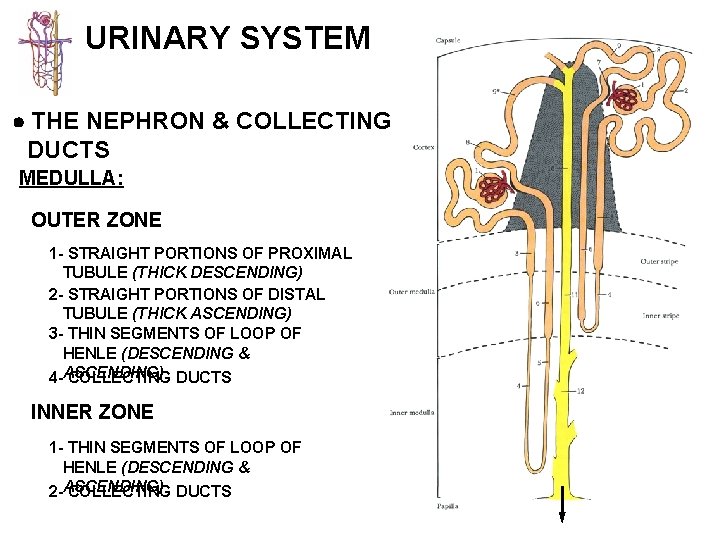

URINARY SYSTEM THE NEPHRON & COLLECTING DUCTS MEDULLA: OUTER ZONE 1 - STRAIGHT PORTIONS OF PROXIMAL TUBULE (THICK DESCENDING) 2 - STRAIGHT PORTIONS OF DISTAL TUBULE (THICK ASCENDING) 3 - THIN SEGMENTS OF LOOP OF HENLE (DESCENDING & 4 -ASCENDING) COLLECTING DUCTS INNER ZONE 1 - THIN SEGMENTS OF LOOP OF HENLE (DESCENDING & 2 -ASCENDING) COLLECTING DUCTS

URINARY SYSTEM THE NEPHRON & COLLECTING DUCTS MEDULLA: OUTER ZONE 1 - STRAIGHT PORTIONS OF PROXIMAL TUBULE (THICK DESCENDING) 2 - STRAIGHT PORTIONS OF DISTAL TUBULE (THICK ASCENDING) 3 - THIN SEGMENTS OF LOOP OF HENLE (DESCENDING & 4 -ASCENDING) COLLECTING DUCTS INNER ZONE 1 - THIN SEGMENTS OF LOOP OF HENLE (DESCENDING & 2 -ASCENDING) COLLECTING DUCTS